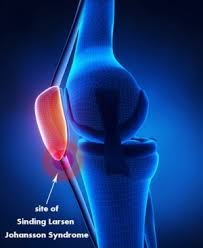

A growth plate is a layer of cartilage near the end of a bone where most of the bones growth happens. Sinding-Larsen Johansson Disease SLJ is a possible cause of knee pain in 8-to-13-year-old active individuals. Figure 1 Anatomy of Sinding-Larsen-Johansson disease.